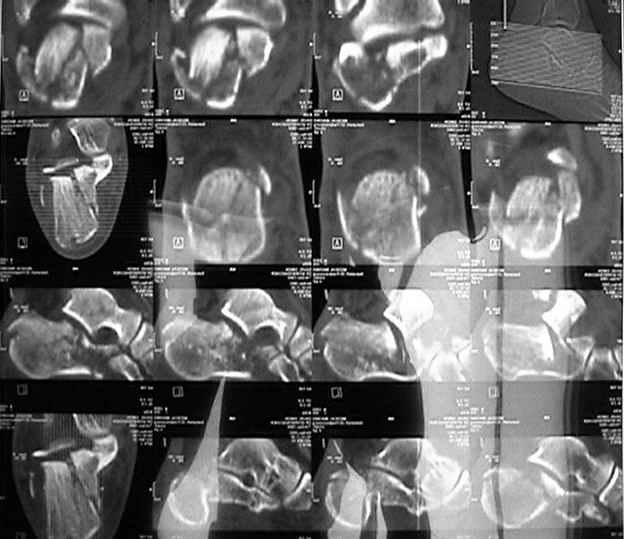

Стандартные проекции не дают полной информации о тяжести повреждения таранно-пяточного сустава.

Решая вопрос о возможности реконструкции необходимо выполнение компьютерной томографии, которая даст ясную картину тяжести повреждения сустава (два фрагмента или несколько) и соответственно спланировать реконструкцию.

3 тип требует открытой репозиции. На томограммах при таком типе перелома суставная поверхность расколота на два или 3 фрагмента с импакцией

КТ.

Кликните для загрузки файла calcaneus2.jpg

Судя по вашим рентгенограммам, восстановить суставную поверхность таранно-пяточного и пяточно-кубовидного сустава полностью не удалось, хотя угол Белера выглядит гораздо лучше, чем на предоперационной рентгенограмме,

что решает проблему посттравматического плоскостопия, восстановлена длина пяточной кости. Жаль, что возникла проблема с качеством томогафии. Интересно было бы знать, на сколько фрагментов была *расколота* суставная фасетка